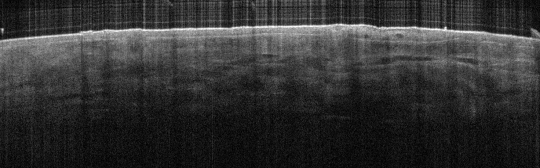

VA34: Right Temple, Actinic Keratosis, Hypotrophic, Focally reaching the base.

- White arrow denotes hair follicle

VA34: Right Temple, Adjacent, Normal

- Note normal hair follicle presentation